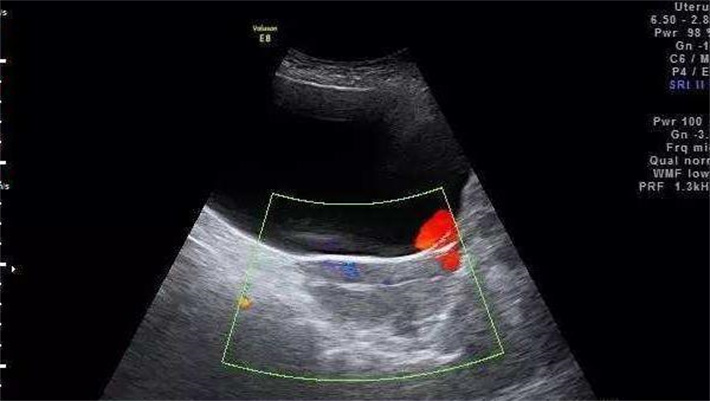

1、内膜血流指数(RI/S)

内膜血流指数(RI/S)是反映子宫内膜血流灌注情况的关键指标。RI指的是阻力指数,S则代表收缩期峰值流速,RI/S通过两者的比值,直观地展现出子宫内膜血管的阻力以及血流供应状况。当RI/S值处于适宜范围时,意味着子宫内膜有着良好的血流灌注,能够为胚胎着床和发育及时输送氧气和营养物质。研究表明,RI/S值在一定程度上与胚胎着床率呈正相关,当RI/S值过高,表明子宫内膜血管阻力增大,血流灌注不足,胚胎就难以顺利着床发育,即便着床成功,也可能因营养匮乏而面临发育迟缓甚至流产风险。